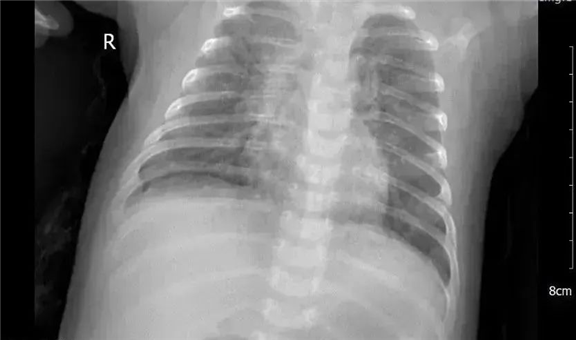

近日,才2个多月的明明(化名)因“反复咳嗽半月余”就诊于我院,门诊考虑“肺炎”收入院,孩子尚小,加上之前一系列治疗无效,这可把新手爸妈急得团团转。住院后检查终于查出背后真凶,原来是沙眼衣原体在捣鬼,孩子确诊沙眼衣原体肺炎,也称“CT肺炎”(Chlamydia trachomatis,CT)。经过我院儿二科医护全力合作,孩子住院1周病情好转出院,家长和孩子露出来久违的笑容。

沙眼衣原体肺炎的大部分患儿早期都表现为双眼分泌物增多等结膜炎症状,病初只有轻微呼吸道症状(鼻塞、流涕),后逐渐加重,大多数无发热,表现为反复的短促咳嗽、呼吸急促。病程迁延,常达数周,如果没有得到适当处理,咳嗽会延续长达2个月。沙眼衣原体肺炎的患儿一般经药物治疗就能治愈,但若存在混合感染或合并其他并发症者,治疗效果则较差。